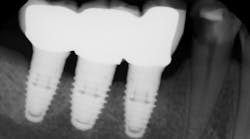

Because ICL between an implant restoration and an adjacent tooth has been highly correlated with the development of caries, a significant health concern arises in individuals with high caries rates who are receiving dental implants (figure 1). Clinicians and allied personnel should be familiar with the factors that contribute to implant-induced decay and are more likely to predispose patients to open contacts. Otherwise, vulnerable patients could be missing out on valuable screening and preventive measures.

Figure 1: Interproximal contact loss between an implant restoration and an adjacent tooth.